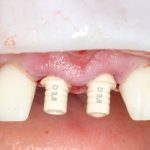

Вот пример. В нашей клинике мы используем три имплантационные системы компании Dentsply Sirona Implants: XiVE, Ankylos и Astratech. Они существенно различаются по макродизайну. Более того, в отличие от субгингивальных XiVE и Astratech, Ankylos — это субкрестальная система, предполагающая погружение платформы ниже уровня альвеолярного гребня.

Это значит, что использовать имплантаты Ankylos при расстоянии до дна синуса менее 2 мм будет проблематично (но возможно, см. клинический пример). Там, конечно, есть специальные заглушки и всё такое… но, к чему этот геморрой?

Импланты Astratech Osseospeed TX, имеющие расширяющуюся пришеечную часть (4,5 и 5.0 мм) также использовать в таких условиях (1-2 мм до дна) сложновато. И дело тут уже не в имплантате, а в хирургическом протоколе — чуть перекрутил кортикальной фрезой, и имплант проваливается в пазуху

Зато в таких условиях отлично стабилизируется XiVE и, внезапно, Nobel Replace, еще внезапнее — Dentium (последние два мы не используем в практике):